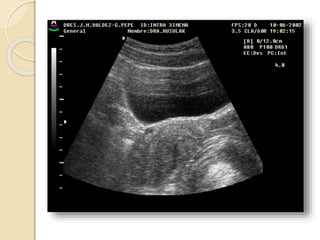

Ecografia tocoginecologica